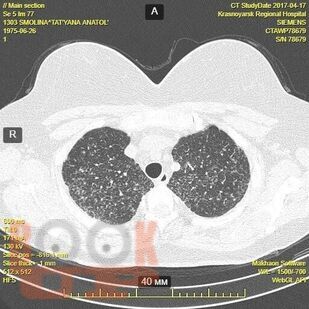

Гранулематозные заболевания легких

Гранулематозные заболевания легких : учебное пособие / И. В. Демко, Н. В. Гордеева, М. Г. Мамаева и др. - Красноярск : КрасГМУ, 2022. - 167 c. - Текст : электронный // ЭБС "Букап" : [сайт]. - URL : https://www.books-up.ru/en/book/granulematoznye-zabolevaniya-legkih-19634258/ (дата обращения: 19.04.2026). - Режим доступа : по подписке.

Учебное пособие предназначено для врачей общей практики, участковых терапевтов, аллергологов, пульмонологов. В настоящем учебном пособии освещены принципы ведения пациентов с диссеминированными заболеваниями легких. Обсуждаются вопросы этиологии, патогенеза, диагностики, а также основные методы лечения.